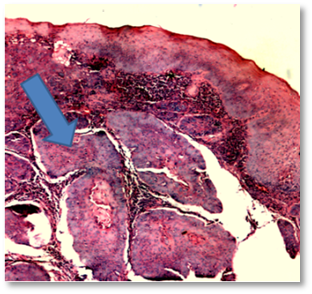

Posteriormente se recibe resultado de biopsia que reporta una neoplasia maligna epitelial con predominio escamoso (80 %), junto a islotes de diferenciación glandular incompleta, infiltrando el estroma (Figura 3y 4, flecha y óvalos azules).